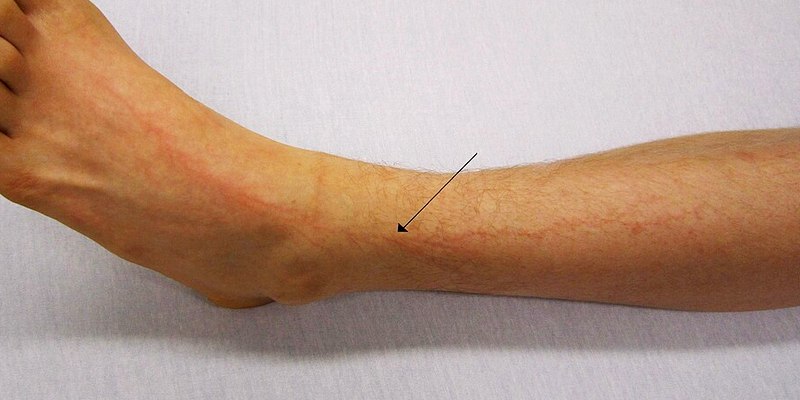

Petir seringkali menyebabkan serangan jantung. Periksa apakah korban bernapas dan cek detak jantungnya. Tempat terbaik untuk memeriksa denyut nadi adalah pembuluh arteri di leher dan di selangkangan.

Jika korban bernapas dengan normal, carilah kemungkinan cedera lainnya. Petir dapat menyebabkan luka bakar, syok, dan kadang cedera benturan. Obati setiap cedera ini dengan pertolongan pertama dasar sampai bantuan medis tiba.

Apa dampak jika tersambar petir juga dapat menimbulkan luka bakar, syok, dan cedera benturan. Korban bahkan mungkin mengalami gejala mirip stroke—mati rasa, lemas, kebingungan, dan wajah terkulai.

Tidak semua arus listrik dari petir benar-benar mengalir melalui orang yang tersambar. Saat tersambar, tegangan antara kepala dan kaki meningkat dengan cepat sehingga menyebabkan gangguan listrik di seluruh permukaan tubuh. Hal ini mengalihkan banyak arus listrik ke kulit, yang dapat menyebabkan luka bakar, tapi juga bisa membantu menjauhkan arus terbesar dari organ-organ dalam tubuh.